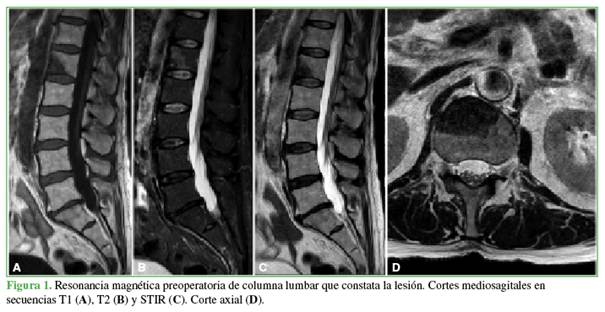

Imágenes posoperatorias

En una tomografía computarizada, se confirma la correcta posición de los tornillos y la ausencia de fuga de cemento intracanal (Figura 2). No se observan signos de compresión del canal vertebral.